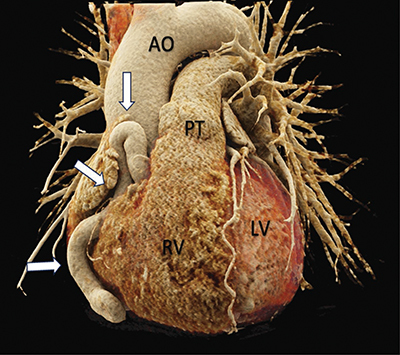

Teaching points: A coronary artery fistula (CAF) is an uncommon anomaly characterized by a diverse clinical spectrum, ranging from asymptomatic cases to severe complications, including heart failure and myocardial infarction.